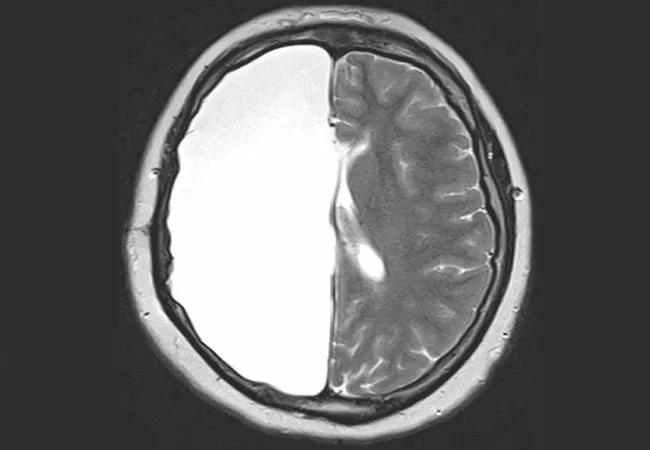

Performing Hemispherectomy in Adulthood Doesn’t Compromise Seizure Freedom Rates

Long-term freedom from seizures and functional outcomes for adults following hemispherectomy are similar to those reported in patients undergoing the surgery during infancy or childhood. So finds a newly reported review of Cleveland Clinic experience with the procedure in adults, which also revealed prognostic indicators of postoperative outcomes.

“Hemispherectomy is rarely performed after childhood for refractory epilepsy, when it is feared that risks to language, cognition and motor skills may be too high,” says Cleveland Clinic epileptologist Ahsan N. V. Moosa, MD, primary investigator of the study, which was published in Epilepsia (2019 Nov 2 [Epub ahead of print]) and presented on December 7 at the American Epilepsy Society’s 2019 annual meeting. “But we found that this surgery is also safe and effective after age 16, and we identified factors that can inform preoperative counseling.”

When indicated for refractory epilepsy secondary to a large, unilateral hemispheric lesion, hemispherectomy is usually performed in infancy or childhood to take advantage of the time of optimal neural plasticity. Long-term seizure freedom rates following hemispherectomy in childhood are reported to be about 66% to 80%. Because the procedure is so uncommonly performed in older age groups, less is known about immediate outcomes in this setting, and no longitudinal data were available.